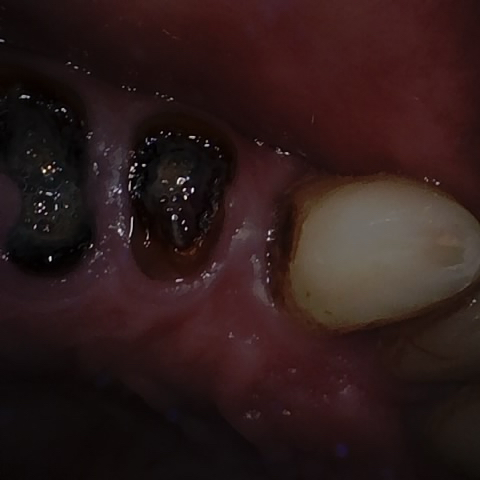

Annotated as "Good"